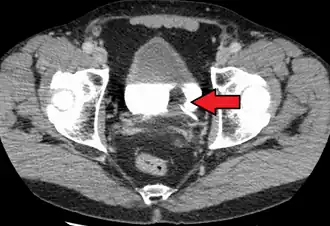

| Carcinoma de células de transição. O branco na bexiga é o contraste. | |

Os fatores de risco para o câncer de bexiga incluem o tabagismo, histórico familiar, antes da terapia de radiação, infecções da bexiga frequentes, e a exposição a determinados produtos químicos.[1] O tipo mais comum é o carcinoma de células de transição. Outros tipos incluem o carcinoma de células escamosas e adenocarcinoma.[3] O diagnóstico normalmente realizado pela cistoscopia com biópsias de tecido.[4] O estágio do câncer normalmente é determinado pelo imagiologia médica, tais como tomografia computadorizada e cintilografia óssea.[1]